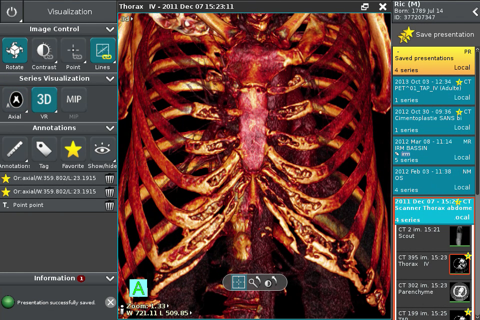

Anywhere Streaming is a DICOM visualization client that connects to Anywhere Server. It provide standard medical image navigation tools surch as : slicing, windowing, MPR, 3D VR, MIP, oblique ... All standard medical image modalities are ...